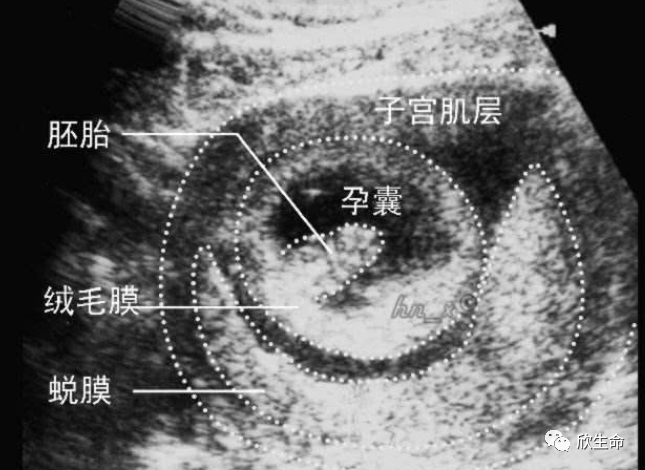

其实,“孕囊”就是超声波显示怀孕的最早迹象之一,也是受精卵着床成功之后形成的最早的怀孕形态。之后随着孕期的增加,胚胎也会逐渐长大,孕囊内会形成胚芽、胎心。

形成胚胎之后,一般是在30-40天左右才会形成胎囊,所以建议在怀孕42天左右,甚至有的孕妈需要45天,再去做B超检查,一般就会能看到完成的孕囊了。

而医生有时看不到孕囊,其实可能由于是孕囊过小,准妈妈可以回家等待几天后再次进行超声检查,虽然这段时间是充满焦虑和煎熬的,但目的是确保100%的准确结果。